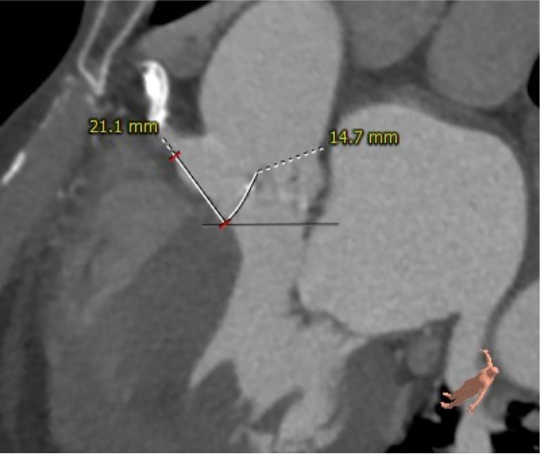

主动脉根部评估:

患者为79岁男性,术前超声心动图提示三叶式主动脉瓣重度狭窄伴中度关闭不全、瓣叶明显钙化增厚、峰值流速 3.63m/s、平均跨瓣压差 33mmHg、有效瓣口面积 0.9cm²;左心扩大,室间隔增厚;二尖瓣中轻度反流、三尖瓣轻度反流;LVEDd:59mm,LVEF:53%。